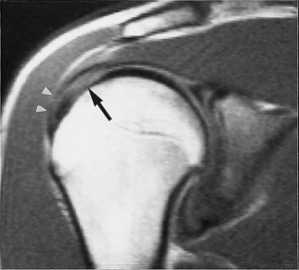

МРТ плечевого сустава с подавлением сигнала от жира. Т2-взвешенная корональная МРТ. Перелом большого бугорка (стрелка).